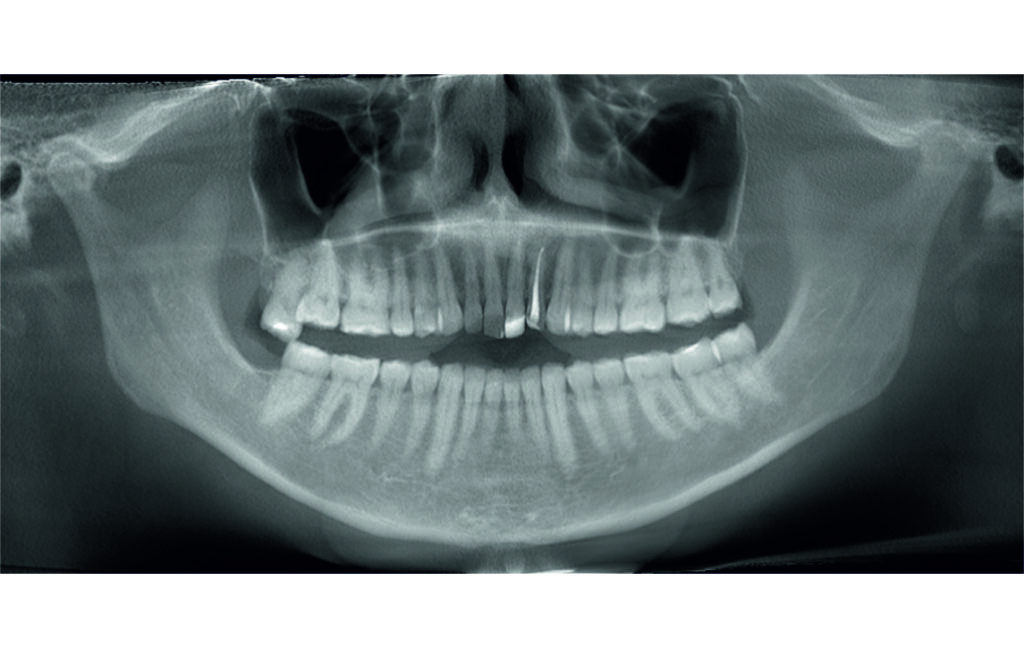

Initial Photos and datas

Angle Class II 2mm on the right, Angle Class II 2mm on the left, light mandibular asymmetry to the right, lower central line 1mm to the right, upper central line 1,5mm to the left, 1mm overjet and overbite. Sagittal asymmetry of upper dental arch. Light crowding upper and lower frontal segments, severe attrition of posterior teeth, night bruxism. Normal sagittal position of both jaws, high angle case, steep mandibular ramus,excessive lower facial height, open bite tendency.

A 1.5 mm deviation of the upper dental midline to the patient’s left was noted, along with a slight mandibular midline shift to the right, likely due to asymmetrical mandibular growth observed in the facial structure. Severe mesial rotations of teeth 16 and 26 were evident in the initial records. As derotation of 16, 26, 17, and 27 progressed up to aligner 16, the premolars in segments I and II moved distally, resulting in a bilateral Class I relationship, as intended in the initial treatment plan.